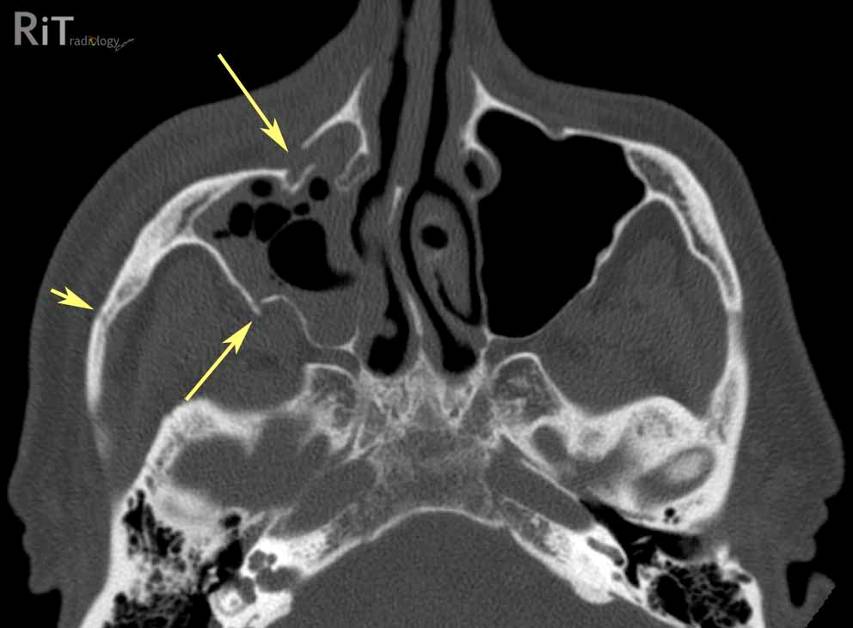

| Battle sign - Think Basilar Skull Fracture | ||||

![]() |